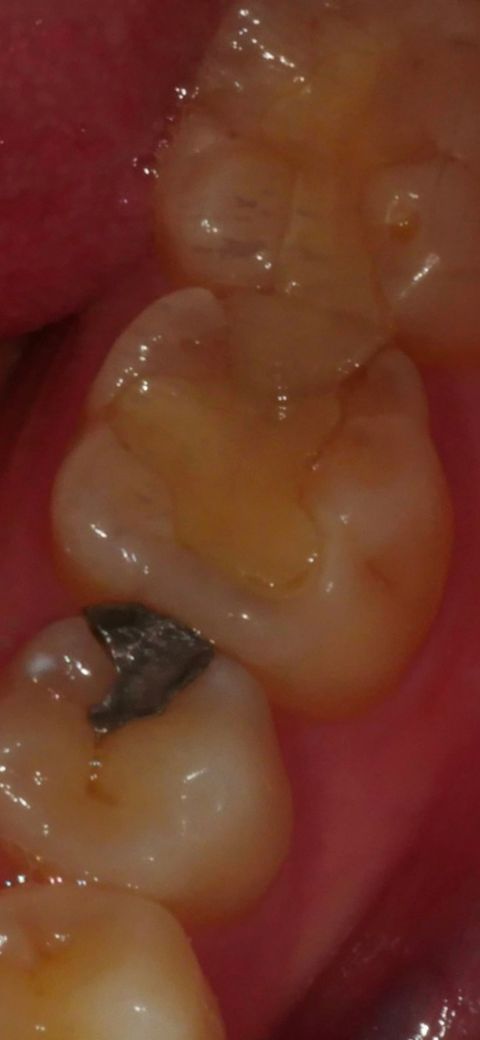

치이 인레이 vs 크라운 해야할까요?

2월 검진했을 때 충치는 없다고 했고 현재 인레이가 깨져있는데 병원에서 크라운 치료 권유 받았습니다ㅠ 인레이교체로 조금 더 써도 될지 아님 범위가 넓어 크라운치료가 나을지 문의드립니다!

• 1번 째 사진

일단은 인레이를 다시 해보시고는게 좋을것같습니다. 하지만, 기존 치료한걸 제거를 해야되니 때문에 신경치료 가능성도 있습니다.

현재 치아의 손상된 정도가 크기 때문에 재치료를 하실 때에는 크라운으로 하시는 게 좋겠습니다.

기존 인레이 크기가 꽤 크긴 하지만 지금 상태에서더 충치가 생기거나 하지 않았다면 다시 인레이 재제작해도 될 것 같습니다

인레이를 해서 파절이 되었다면 인레이로 치료를 하기에는 너무 강한 힘이 작용하고 있다는 것입니다.

이런경우 일반적으로 크라운 치료가 필요할 수 있습니다.